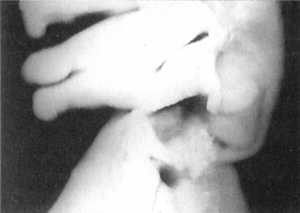

Приняв один из вывихнутых суставов условно за здоровый, хирург производит наклон

головы в его сторону. При этом в условно здоровом суставе соотношение между

суставными отростками остается прежним (рис. 2.12.10, 2.12.12 и рис. 2.11, графа

"наклон головы влево" левый сустав - вид сзади, сбоку и сверху), а

на противоположной стороне сцепившийся вывих переходит в вывих с высоким стоянием

суставных отростков (рис. 2.12.9, 2.12.11 и рис. 2.11, графа "наклон головы

влево", правый сустав - вид сбоку и сзади). Кривая вертикальных перемещений

регистрирует увеличение расстояния между позвонками до 9,3±1,2 мм, что сопровождается

повышением давления внутри модели дурального мешка на 318,25±4,3 мм вод. ст.

по сравнению с исходным. В позиции сверху соотношение суставных отростков остается

прежним.

Рис. 2.12.9. Наклон головы влево. Правый

сустав. Вид сбоку |

Рис. 2.12.11. Наклон головы влево. Правый

сустав. Вид сзади |

Рис. 2.12.10. Наклон головы влево. Левый

Рис. 2.12.12. Наклон головы влево, Левый